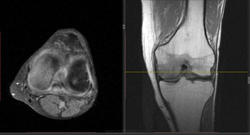

Мужчина 1963 г.р. Жалуется на боль в левом коленном суставе около 6 мес, в последний месяц стало совсем тяжко. Со слов заболел зимой, когда во время прогулки коленки сильно замерзли. Сам думаю на асептический некроз, но смущает множественность поражения.

Дмитрий, я в заболеваниях суставов не дока, но трабекулярный отек вкупе с выпотом может быть обусловлен воспалительными изменениями , но полностью начальные проявления аваскулярного некроза не могу отрицать.

я бы не поставил аваскулярный некроз. если исключена травма, дифференцировать с артритом.

Хрящ не поврежден, для артрита...